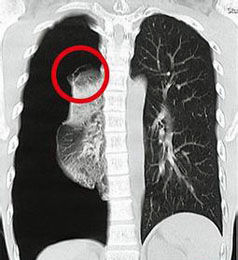

檢查

首先必須排除心源性因素,做心電圖、平板試驗、超聲心動圖等。內科檢查是常規檢查的項目里必查的檢查項目之一,通過病史詢問,了解受檢查者的重要疾病,並評估檢查者體質及營養情況,綜合評估健康狀況。胸壁檢查是胸部檢查中重點的一項檢查,一般包括營養狀態、皮膚、淋巴結和骨骼肌發育等,此外重點檢查靜脈、皮下氣腫、胸壁壓痛、肋間隙等。X線檢查可初步發現胸部腫瘤、肺炎、氣胸、肋骨骨折,CT及三維成像可確診;MRI可發現肋軟骨炎症及腫瘤;胃鏡檢查發現食管反流及食管疾病。

胸膜炎、胸膜結核、膿胸、氣胸、肺膿腫潰破可行胸腔沖洗引流,肺癌及胸膜間皮瘤可行腫瘤冷凍治療,化療、中藥辨證治療予以配合。